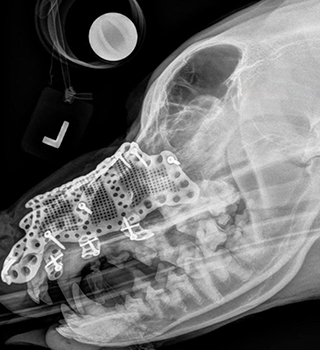

A seven-year-old Bernese Mountain Dog with a tumour on the left side of his maxilla (upper jaw) had few options other than total excision of the growth followed by reconstruction. A customised 3D printed titanium implant supporting the dog's bone structure was the most appropriate treatment due to the complexity of the region, requiring significant design and manufacturing freedom.

The procedure, which was carried out by Julius Liptak, veterinary surgeon at Alta Vista Animal Hospital in Ottawa, Canada, used an additively manufactured titanium maxillofacial implant designed by Voxelmed, based in Germany.

Using Digital Imaging and Communications in Medicine (DICOM), a standard that enables the integration of medical imaging devices, a digital 3D model of the dog's affected area was generated. The model was used to design a custom implant with input from Dr. Liptak.

During the design of the implant, Dr. Liptak reviewed the design repeatedly to compare it to 3D scans and models of the dog's skull. This made the process of manufacturing and placement much more straightforward, as it met the surgeon's specifications for how the implant would fit.

“During surgery, the affected areas, along with clean tumour margins, were removed,” explained Jan Klasen, veterinary surgeon, 3D designer and CEO of Voxelmed. “Because the tumour occurred in the skin, rather than the maxillary bone, resection involved a revision maxillectomy with excision of the 45 mm x 50 mm mass, with 30 mm lateral margins. The implant was then put into place and fixed with surgical screws. A facial axial pattern skin flap was prepared and used to cover the affected area and the implant. This left the dog with a particularly impressive physical outcome as the nose structure did not have to be altered to account for the missing tissue.

Without additive manufacturing technology, it would have been almost impossible to reconstruct the dog's maxilla after tumour removal, because the area was extremely complex in geometry,” Klasen commented. “The implant had to have a similar shape and functionality as the dog's existing bone structure. Using additive manufacturing to maintain the original shape and function of the oral and nasal cavity ensures a high quality of life for the dog, just as a naturally shaped skull and maxilla helps the dog to breathe and eat easily.